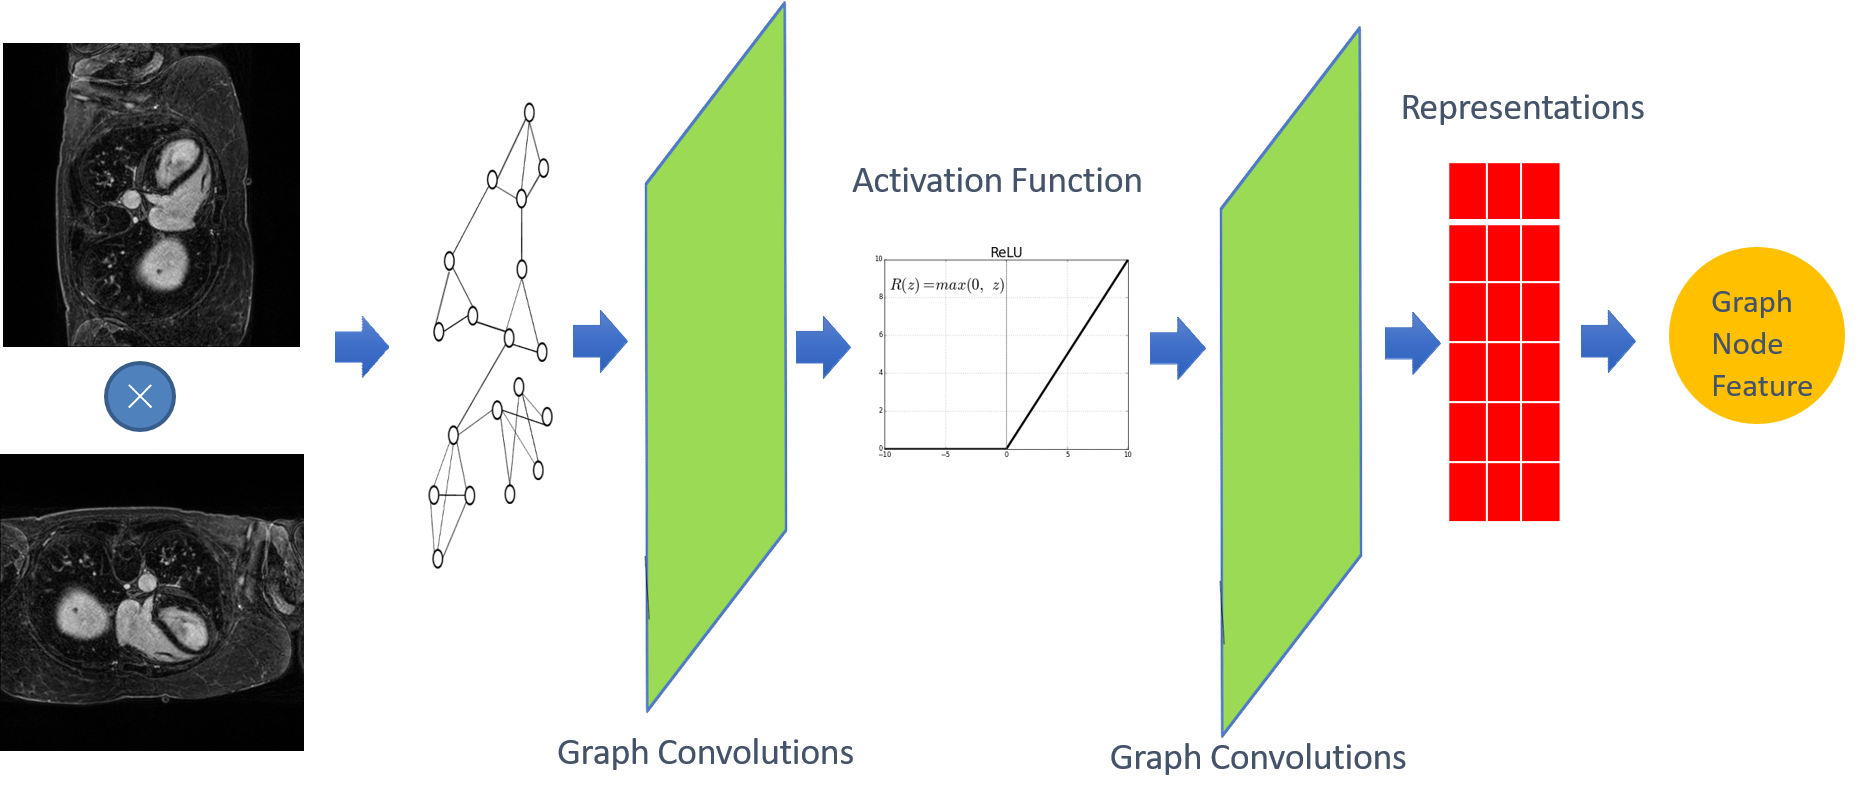

2.2 Bridge

The bridge module is added to the skip connection from the original U-Net [22] with a GCN transformation (seen in Fig. 5).

It bridges the encoder with ETB and the decoder constructed by convolutions to maximize the advantages brought by transformers and convolutions. It is capable of promoting the optimization of local features and generalization across data from different domains.

GCN in Fig. 5 (see detail structure in Fig. 7) is to extract the spatial features of topological graphs by using the topologically-stable relationship information. Meanwhile, after convolutional graph operation, pixels feature belonging to the same class in semantic segmentation will be close to each other in the feature manifold (see Fig. 6).

We multiplied the feature map with the corresponding transpose as input of the GCN block. Global features will be generated by two layers of GCN blocks (see Fig. 7), while the global topological relationship of graph structure-based features (see Fig. 6) is obtained. The final feature map is fused by adding (see Fig. 5) the encoder output and the global relationship node feature together.